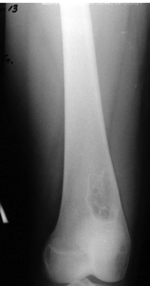

Для проведения ревизионного эндопротезирования тазобедренного сустава с дефектами дна и стенок вертлужной впадины был предложен вариант ДКИ с высокой степенью деминерализации. Их особенностью явилось то, что источником донорских тканей явились кости свода черепа. Трехслойная структура и выраженные эластичные свойства делают материал удобным для замещения значительных по площади и сложных по конфигурации дефектов в области тазобедренного сустава [2]. К сожалению, проблемы ревизионного эндопротезирования тазобедренного сустава нарастают с каждым годом по мере расширения показаний и проведения первичных операций эндопротезирования крупных суставов (рис. 3).

Наличие значительных разрушений костной ткани диктует поиск и необходимость выбора материала для проведения аллопластики. Уже сейчас в клиниках ЦИТО в области тазобедренного сустава со все большим постоянством используют ДКИ в виде пластин и костной стружки высокой степени деминерализации. С этой же целью применяют аллоимплантанты, полученные после технологической обработки головок бедренных костей, удаленных у других пациентов в ходе операции по поводу перелома шейки бедренной кости или коксартроза. Отбор пригодных головок для дальнейшего изготовления из них аллоимплантантов проводится на основе результатов морфологических исследований: обязательного наличия сохранной формы, отсутствия грубой деформации, признаков некроза, остеопороза и обширных кистозных полостей.